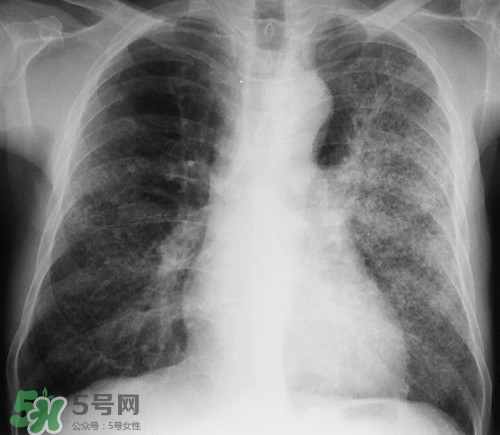

肺炎是常見(jiàn)的呼吸道感染疾病,這病也確實(shí)麻煩,如果處理不當(dāng)可能危及生命哦,那么肺炎會(huì)不會(huì)傳染呢?吃什么好的快呢?下面我們來(lái)介紹下吧!

--會(huì)傳染.所以平時(shí)要注意防護(hù),肺炎一般是10天到15天才能治好,治療是需要一個(gè)過(guò)程的.先發(fā)燒之后有痰,咳嗽是為了把痰液咳出,之后慢慢就會(huì)好起來(lái)的.會(huì)引發(fā)高燒的.

--肺炎多是細(xì)菌感染,不會(huì)傳染,一般肺炎可引起發(fā)熱、咳嗽、胸痛,肺炎經(jīng)抗生素治療后,七至十天之內(nèi),多可治愈,您可休息10天至半月,注意保暖

--肺炎是細(xì)菌感染引起,可隨呼吸排出到空氣中,如果在一個(gè)屋子里空氣不暢,容易造成細(xì)菌密度增加,這是抵抗力低的人是容易感染的,當(dāng)然肺炎如果得不到及時(shí)治療可以引起高燒的.